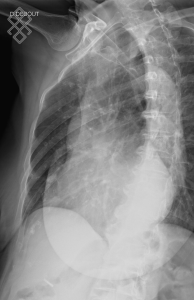

Radiographie du Gril costal